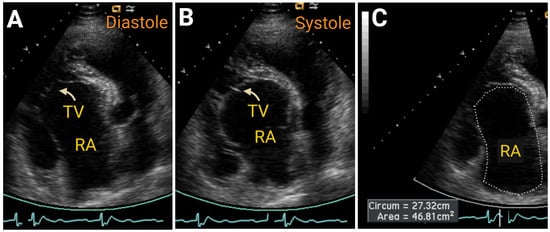

| Area, cm2 | <19 | 19 to 22 | 23 to 24 | >24 | ||